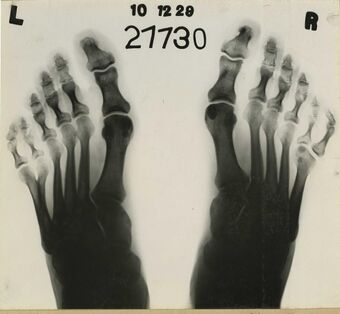

| Foot postaxial polydactyly |

Scalp defects-postaxial polydactyly syndrome is a very rare genetic disorder which is characterized by congenital defects of the scalp and type A postaxial polydactyly.[1][2] An additional finding is severe intellectual disability. It is thought to be inherited in an autosomal dominant manner. Approximately 9 cases from two families have been described in medical literature.[3][4][5]